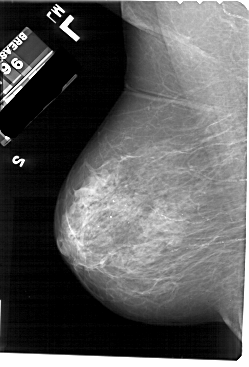

A_1697_1.RIGHT_MLO

RIGHT_MLO LINES 5491 PIXELS_PER_LINE 3856 BITS_PER_PIXEL 12 RESOLUTION 43.5 OVERLAY